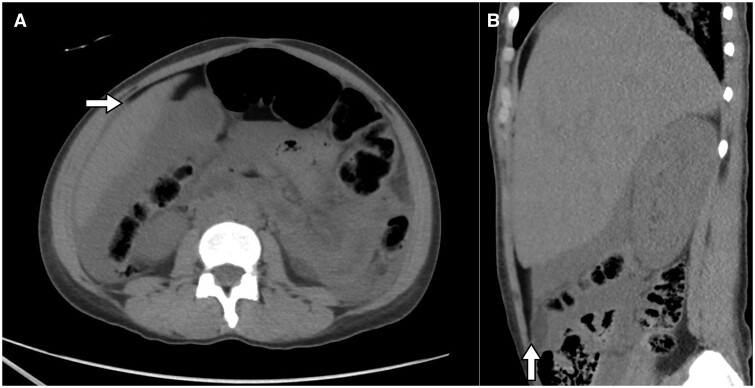

Spontaneous rupture of ovarian dermoid cysts is uncommon. We describe a case of a 32-year-old female who presented to the emergency room with abdominal pain and distension. The patient was discovered to have a ruptured dermoid cyst which caused chemical peritonitis and was managed surgically.